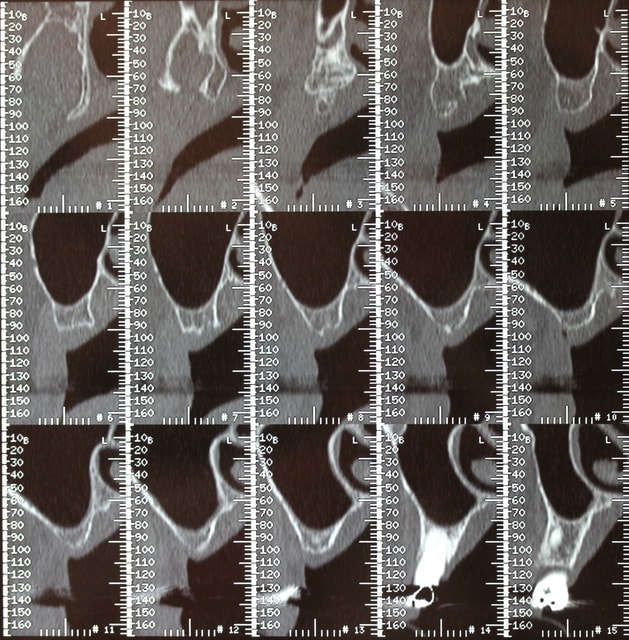

Le dentascan de la mandibule pour que vous compreniez mieux la difficulté...quais impossible de la considérer en cylindres même en déplaçant le NDI vous n avez aucune hauteur exploitable... Même des lame de Likow n y passent pas et les sous périostés sont interdits en Europe

J ai perdu mes deux foutus cylindres et ai dû les remplacer par deux double disk...et changer les deux mono disk du secteur droit

Et oui l implanto basale n est pas non plus un long fleuve tranquille

21/08/2013 à 19h06

La mandibule est faite

Ostéotension maxillaire en cours

Implanto maxillaire en nov 2013

Le scan pour vous faire patienter